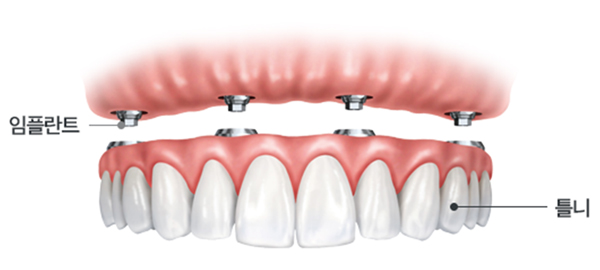

치아를 모두 상실한 경우 필요한 만큼의 임플란트를 식립하여, 치아 전체의 기능을 할수 있도록 합니다.

전체치아의 기능을 회복시켜주기 위해, 치아의 균형을 고려하여 정확하게 식립해야 합니다.

임플란트 개수를 아래 치아 6~12개, 위 치아 8~12개 정도로 줄여

그 사이를 치아 모양으로 튼튼히 연결

잇몸뼈에 임플란트를 식립 후 고정성 보철물을 연결하는 방식!

틀니보다 힘이 훨씬 좋고 내 치아처럼 사용할 수 있으며

전체 치아 기능의 90% 정도로 회복이 가능합니다.

최소 6개 정도 임플란트를 식립 한 후

틀니 형태의 보철물을 임플란트에 고정시키는 방법으로

틀니를 조금 더 편하게 사용할 수 있는 방법입니다.